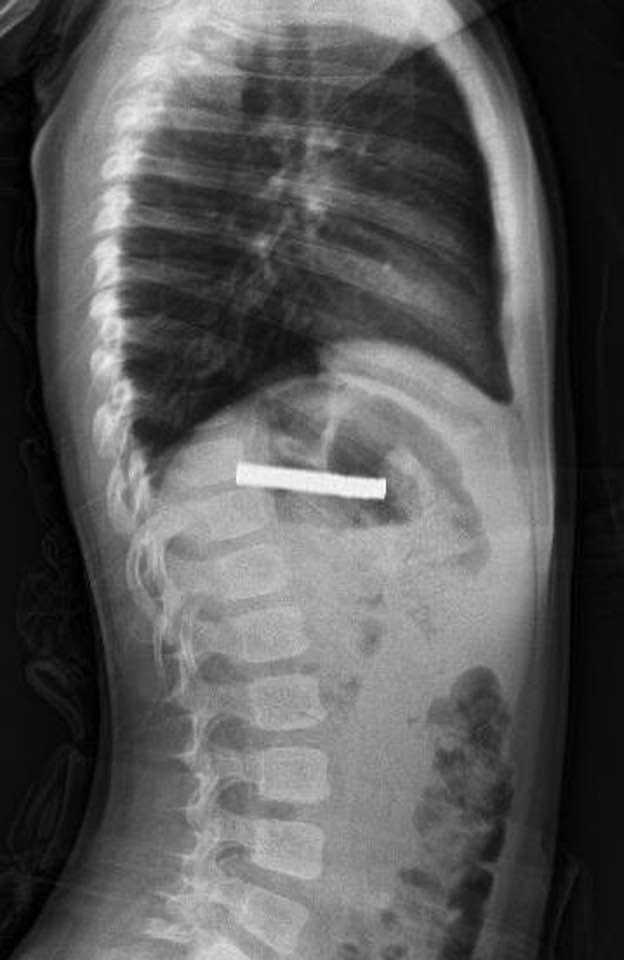

Edinilen bilgiye göre, Erzurum’da bir çocuk evde bulunan 19 tane mıknatısı yuttu. Çocuğun rahatsızlanması sonucu durumu öğrenen aile hastaneye başvurdu. Daha sonra çocuk Elazığ’a sevk edildi. Fırat Üniversitesi Çocuk Gastroenteroloji Hepatoloji ve Beslenme Bilim Dalı Başkanı Prof. Dr. Yaşar Doğan, çocuk hastanın yemek borusuna yapışmış 19 mıknatısı endoskopik yöntemle çıkardı.

Mıknatıslar uzun süre yemek borusunda takılı kaldığı için yemek borusu ve mide girişinde zedelenmeler olurken, çocuğun sağlık durumunun iyi olduğu ve taburcu edildiği öğrenildi.